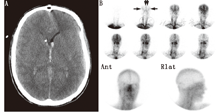

(4)脂溶性放射性药物。从20世纪80年代中期开始[72,73,74],脂溶性放射性核素99Tcm-HMPAO[75,76,77,78,79]和99Tcm-bicisate[47,48,80]跨越血-脑屏障经相关代谢后滞留于脑间质,从而可用于诊断脑死亡。即使在代谢功能紊乱时,此类探针也可滞留于脑间质[78,79]。其与4支脑血管对比造影术有较好的相关性[81]。通过显像可获得早期血流相和随后的血池相;但只要其中任何一相有血流存在,则均不支持脑死亡诊断(图3,图4)。99Tcm-HMPAO分解较快,需在30 min内注射[82]。随后开发的稳定制剂具有更长的贮存期,但注射时需先通过直径为0.45 μm的过滤装置以排除颗粒物质[83];必须注意确保过滤不妨碍足够的"弹丸"注射剂量。

静态血池相更为灵敏,且重要的是其对后颅窝的评估能力(图5);动态血流相主要反映脑前部情况,不能反映血池相信息[79,84]。临床研究主要使用延迟显像来评估脑血流灌注情况[77,78,85,86]。de la Riva等[79]的研究表明血流相无法显示的血流情况在静态血池相中小脑灌注很清晰。此外,由于血池相较血流相可以获得更高的放射性计数,因此图像的灵敏度更高。血池相对"弹丸"注射技术和注射时间的依赖性较小;还可进行重复显像及断层显像[87,88,89]。除外血池相无显像的罕见情况,99Tcm-HMPAO准备失败会导致动态血流图像的摄取值持续残留[20,78,79,80,81,82,83,84,85,86,87,88,89,90]。